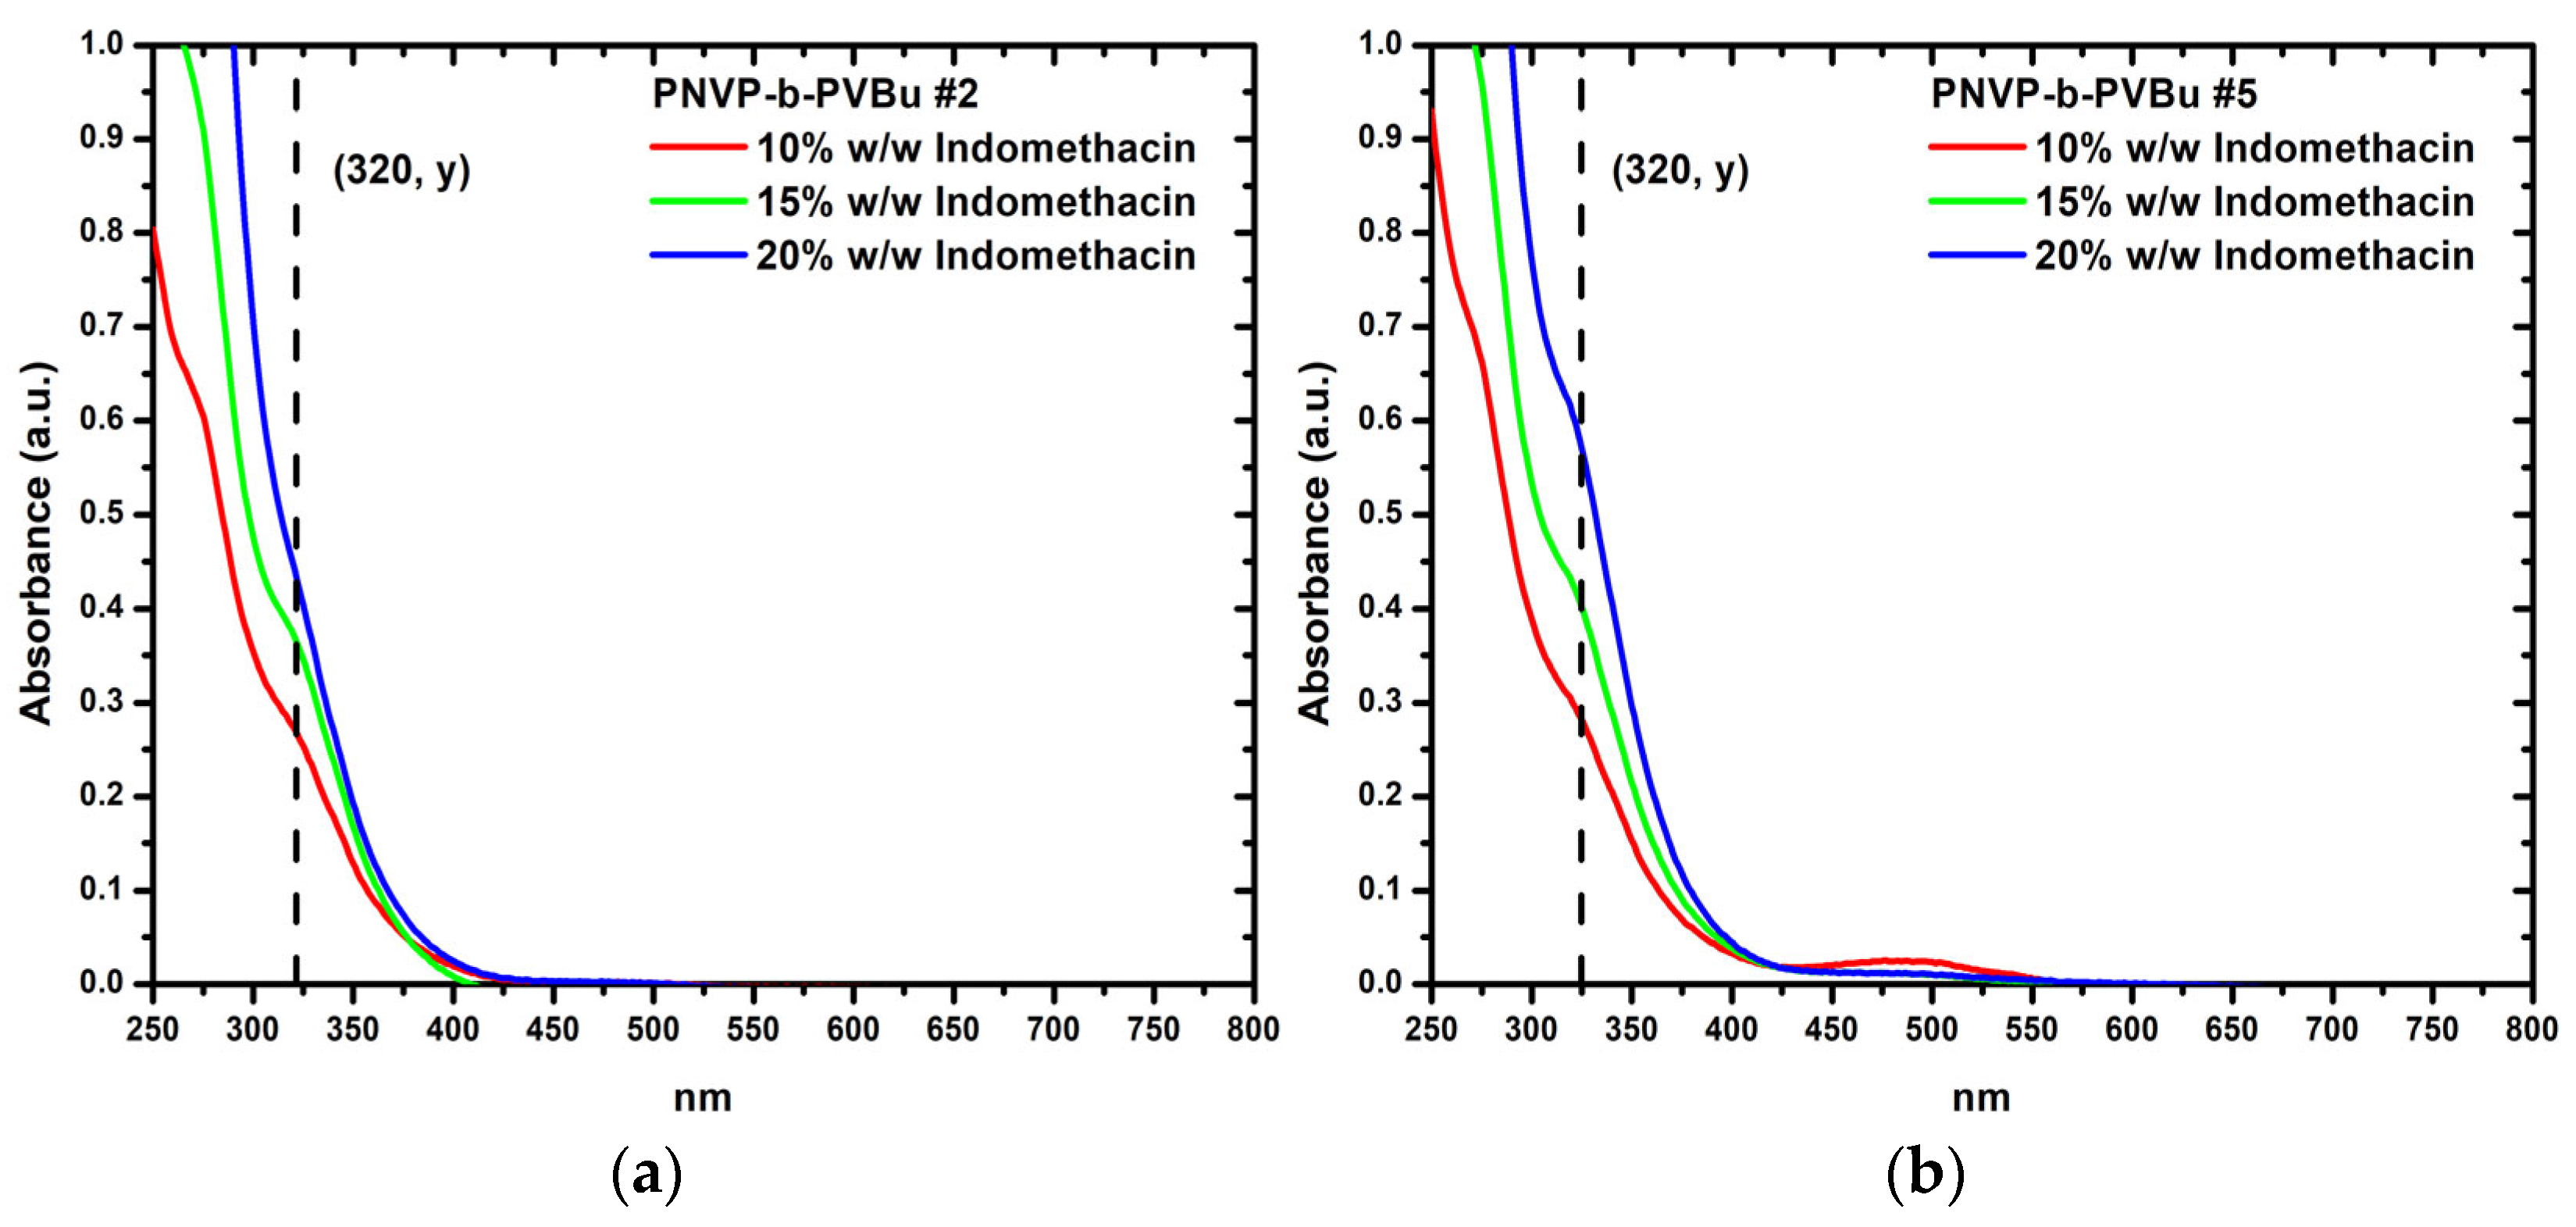

3.3.2. Encapsulation of Indomethacin

| Sample | Ind. 1 (w/w) | A 2 (a.u.) | Pol. 3 (μg/mL) | DIF 4 (μg/mL) | LD 5 (μg/mL) | DLC (%) | DLE (%) |

|---|---|---|---|---|---|---|---|

| PNVP-b-PVBu #1 | 10% | 0.32 | 178.34 | 17.16 | 12.53 | 7.02 | 73.00 |

| 15% | 0.69 | 169.51 | 24.48 | 28.93 | 17.07 | 118.17 | |

| 20% | 0.80 | 168.85 | 34.39 | 33.98 | 20.13 | 98.83 | |

| PNVP-b-PVBu #2 | 10% | 0.27 | 168.70 | 15.97 | 10.56 | 6.26 | 66.16 |

| 15% | 0.37 | 164.15 | 25.65 | 14.93 | 9.09 | 58.21 | |

| 20% | 0.45 | 166.63 | 33.01 | 18.24 | 10.95 | 55.26 | |

| PNVP-b-PVBu #3 | 10% | 0.32 | 180.86 | 16.18 | 12.55 | 6.94 | 77.58 |

| 15% | 0.40 | 182.12 | 25.69 | 16.12 | 8.85 | 62.76 | |

| 20% | 0.61 | 187.77 | 34.82 | 25.70 | 13.69 | 73.82 | |

| PNVP-b-PVBu #4 | 10% | 0.30 | 171.48 | 16.54 | 11.90 | 6.94 | 71.95 |

| 15% | 0.32 | 173.91 | 23.46 | 42.45 | 7.16 | 53.07 | |

| 20% | 0.56 | 173.42 | 32.31 | 23.32 | 13.45 | 72.18 | |

| PNVP-b-PVBu #5 | 10% | 0.30 | 165.14 | 15.93 | 11.75 | 7.11 | 73.73 |

| 15% | 0.43 | 165.03 | 24.82 | 17.41 | 10.55 | 70.13 | |

| 20% | 0.61 | 164.20 | 35.00 | 25.46 | 15.51 | 72.75 |